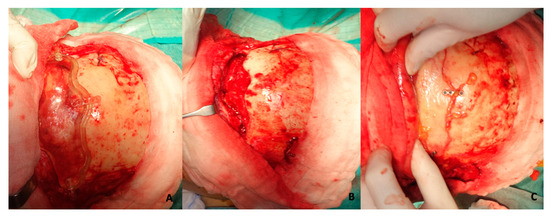

2.3. Surgical Procedure (Employment of Template)